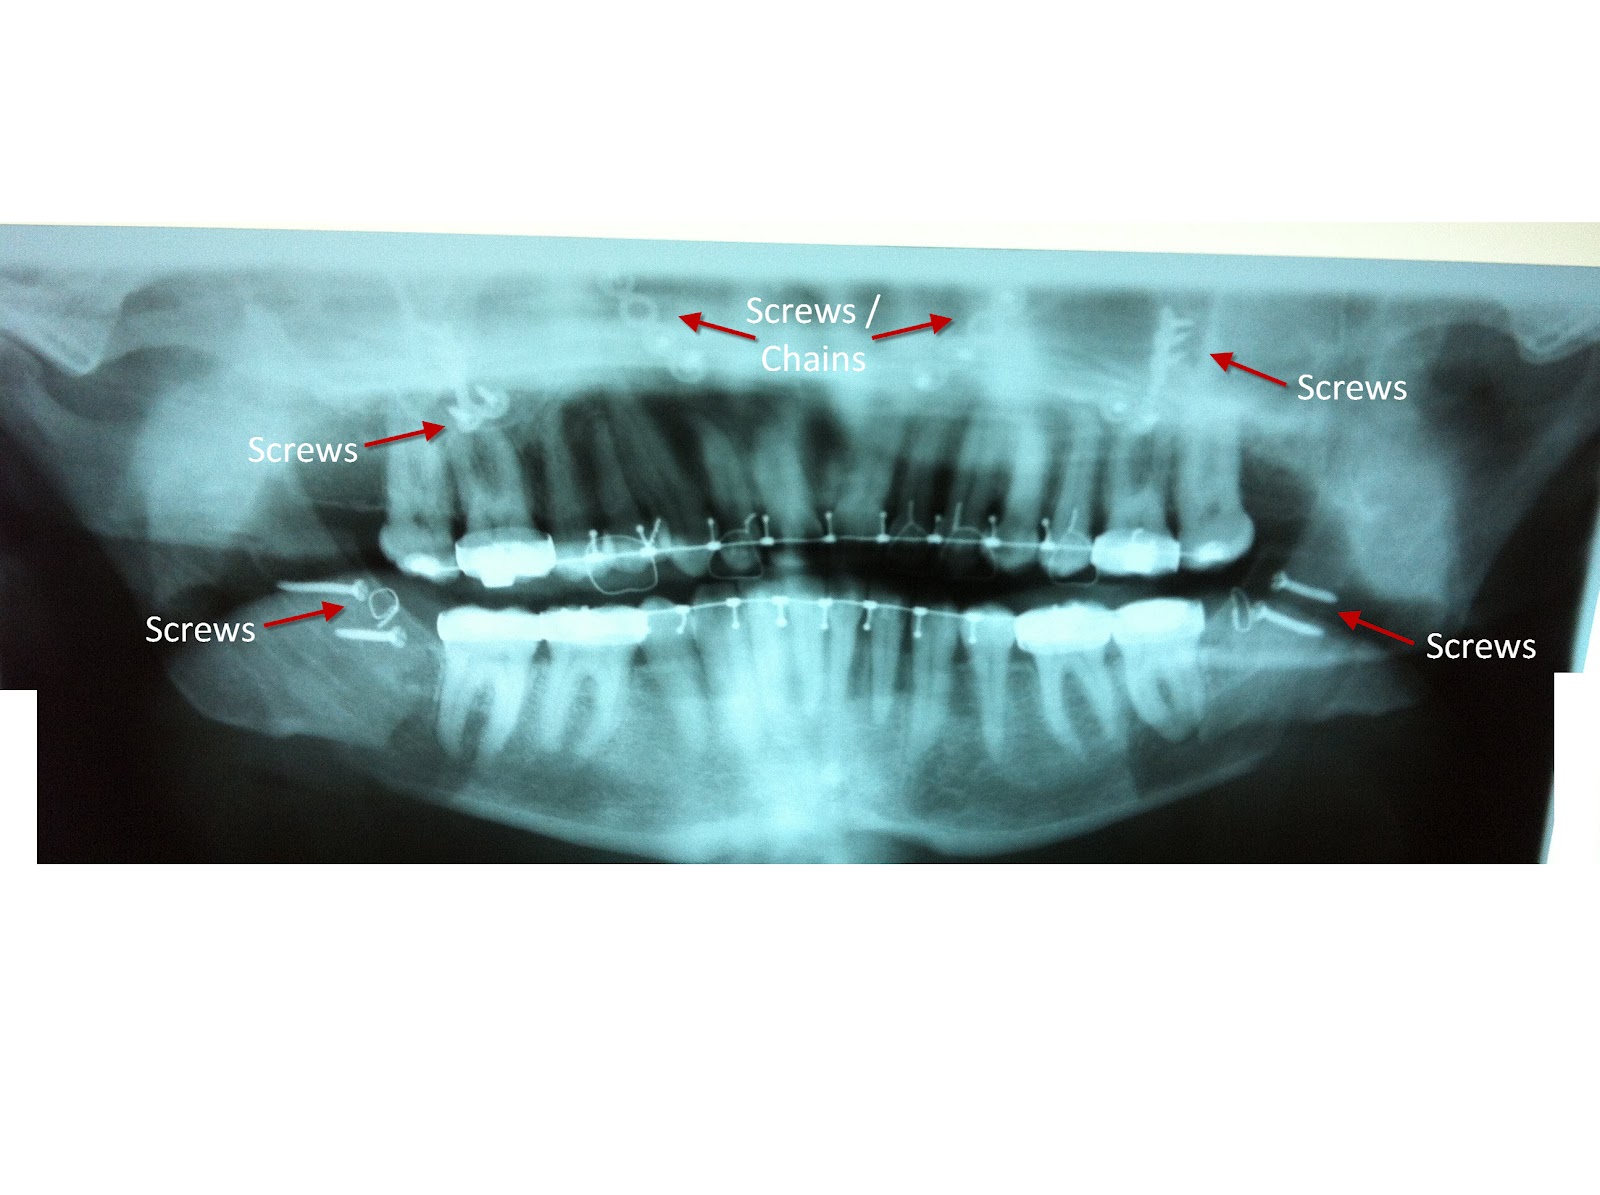

3 month recovery for double jaw surgery Artofit Double Jaw Surgery X Ray Jaw surgery, or orthognathic surgery, corrects jaw problems and related conditions. Learn more about how this surgery works and how we can help. jaw surgery, also called orthognathic surgery, is surgery that helps align your upper jaw (maxilla) and lower jaw. what is double jaw surgery? You can see, quite clearly, the drastic change that took place on. Double Jaw Surgery X Ray.

Before&after double jaw surgery r/XRayPorn Double Jaw Surgery X Ray what is double jaw surgery? double jaw surgery corrects both the upper and lower jaw at the same time. You can see, quite clearly, the drastic change that took place on the operating. Most people undergo jaw surgery to treat. They do a decent job of. Learn more about how this surgery works and how we can help.. Double Jaw Surgery X Ray.

Double jaw surgery with a bit of hip thrown in! Day 49 Seven Weeks On.... Double Jaw Surgery X Ray mouth breathing, dry mouth, jaw pain, difficulty chewing, and an inability to bite led me to double jaw surgery. what is double jaw surgery? You can see, quite clearly, the drastic change that took place on the operating. jaw surgery, also called orthognathic surgery, is surgery that helps align your upper jaw (maxilla) and lower jaw. . Double Jaw Surgery X Ray.

Jaw Surgery Journey Day 18 Before and After Double Jaw Surgery (XRays) Double Jaw Surgery X Ray You can see, quite clearly, the drastic change that took place on the operating. what is double jaw surgery? Most people undergo jaw surgery to treat. jaw surgery, also called orthognathic surgery, is surgery that helps align your upper jaw (maxilla) and lower jaw. They do a decent job of. mouth breathing, dry mouth, jaw pain, difficulty. Double Jaw Surgery X Ray.

Double Jaw Surgery Journey PreSurgery XRays Double Jaw Surgery X Ray jaw surgery, also called orthognathic surgery, is surgery that helps align your upper jaw (maxilla) and lower jaw. mouth breathing, dry mouth, jaw pain, difficulty chewing, and an inability to bite led me to double jaw surgery. what is double jaw surgery? They do a decent job of. double jaw surgery corrects both the upper and. Double Jaw Surgery X Ray.